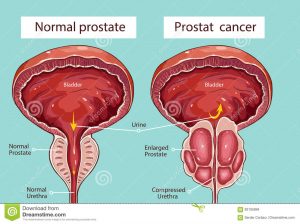

Prostat vəzinin quruluşu

Prostat vəzi –kiçik çanaqda, sidikliyin altında, sidik cinsiyyət diafraqmasının üzərində, qasıq bitişməsinin arxasında, düz bağırsağın önündə yerləşir və boz rəngdə olub sərt konsistensiyalıdır.

Prostat vəzinin çəkisi 20-25 q, köndələn ölçüsü 4 sm, boylama ölçüsü 3 sm, qalınlığı 2 sm qədərdir. Prostat vəzinin əsası sidikliyin yuxarı hissəsinə, zirvəsi isə sidik cinsiyyət diafraqmasına baxır. Prostat vəzinin ön və arxa səthləri vardır. Vəzin ön səthi qasıq bitişməsinə, arxa səthi düz bağırsaq ampuluna söykənir.

Prostat vəzinin adenoması nədir?

Prostat vəzinin adenoması — prostat vəzinin xoşxassəli şişidir. Buna görə də bu xəstəliyin digər rəsmi adı – prostat vəzinin xoşxassəli hiperplaziyası (boyüməsi). Prostat vəzinin adenoması kişilər arasında çox yayılmış xəstəlik olub, adətən, yaşı 40-dan yuxarı olan kişilərdə təsadüf edilir.

Xəstəliyin ikinci mərhələsində sidik ifrazı pozğunluqları daha da artmağa başlayır. Sidik ifrazının tezliyi daha da artır, axşamlar xəstə sidik ifrazına bir neçə dəfə durur. Bəzi hallarda sidik ifrazı dayanmış olur və xəstə uzun müddət sidik ifraz edə bilmir. Xəstədə sidik ifrazının əvvəlində və sonunda ağrı olur, aralıq, qasıq, xayalıq nahiyəsində sızıldayan ağrılar, ereksiya və toxum xaricetmə pozğunluqları baş verir. Kişilərdə normal sidiyə getmə prosesindən sidik kisəsində qalıq sidik qalmamalı və onun həcmi 12 ml-dən az olmalıdır. Prostat adenoması olan kişilərdə isə sidik ifrazından sonra sidik kisəsində 100 ml-dən çox sidik qalması probemin olduğunu göstərir.